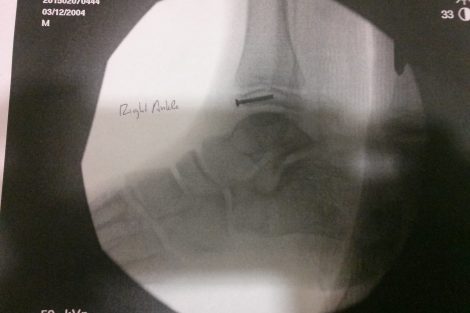

Austin was rushed to the UCD Med Center in Sacramento, where he underwent over 4 hours of surgery to repair the horrifying list of injuries…Broken right femur, Broken right ankle, Broken left tibia and fibula, multiple cuts and bruises to his arms and even his chin.

I spoke with Austin’s mother Ashley Whidden, who said that doctors repaired the injuries with metal plates and screws. The x-rays are horrifying.